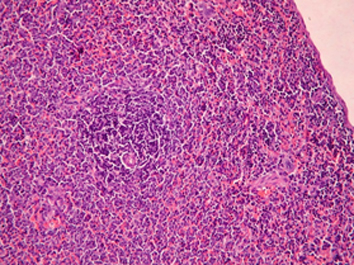

Результаты. Показано, что применение рифабутина в сочетании с аскорбигеном приводит к ослаблению повреждающего действия антибиотика на слизистую оболочку желудочно-кишечного тракта и ускорению процессов восстановления ее структуры, что клинически выражается в нормализации прироста массы тела животных. При комбинированном применении рифабутина с аскорбигеном уменьшается глубина цитопении, а количество лейкоцитов в периферической крови крыс восстанавливается быстрее. Признаки атрофии лимфоидной ткани селезенки отсутствуют. Введение аскорбигена до рифабутина оказывает протекторный эффект в отношении тканей почек и семенников.